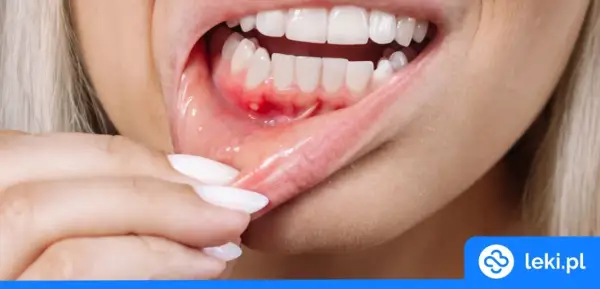

Zapalenie dziąseł: Bakterie zarażają, choroba nie! Jak się chronić?

Czy zapalenie dziąseł jest zaraźliwe? Poznaj różnicę między przenoszeniem bakterii a chorobą. Dowiedz się, jak skutecznie chronić siebie i bliskich!

Od czego puchną dziąsła? Poznaj przyczyny i skuteczne leczenie!

Opuchnięte dziąsła? Poznaj najczęstsze przyczyny, objawy i skuteczne metody leczenia. Sprawdź, jak sobie pomóc i kiedy iść do dentysty.

Ropa w dziąśle: Jak sobie pomóc i kiedy pilnie do dentysty?

Ropa w dziąśle? Sprawdź domowe sposoby na ulgę i leki bez recepty. Dowiedz się, czego unikać i kiedy pilnie do dentysty, by uniknąć powikłań.